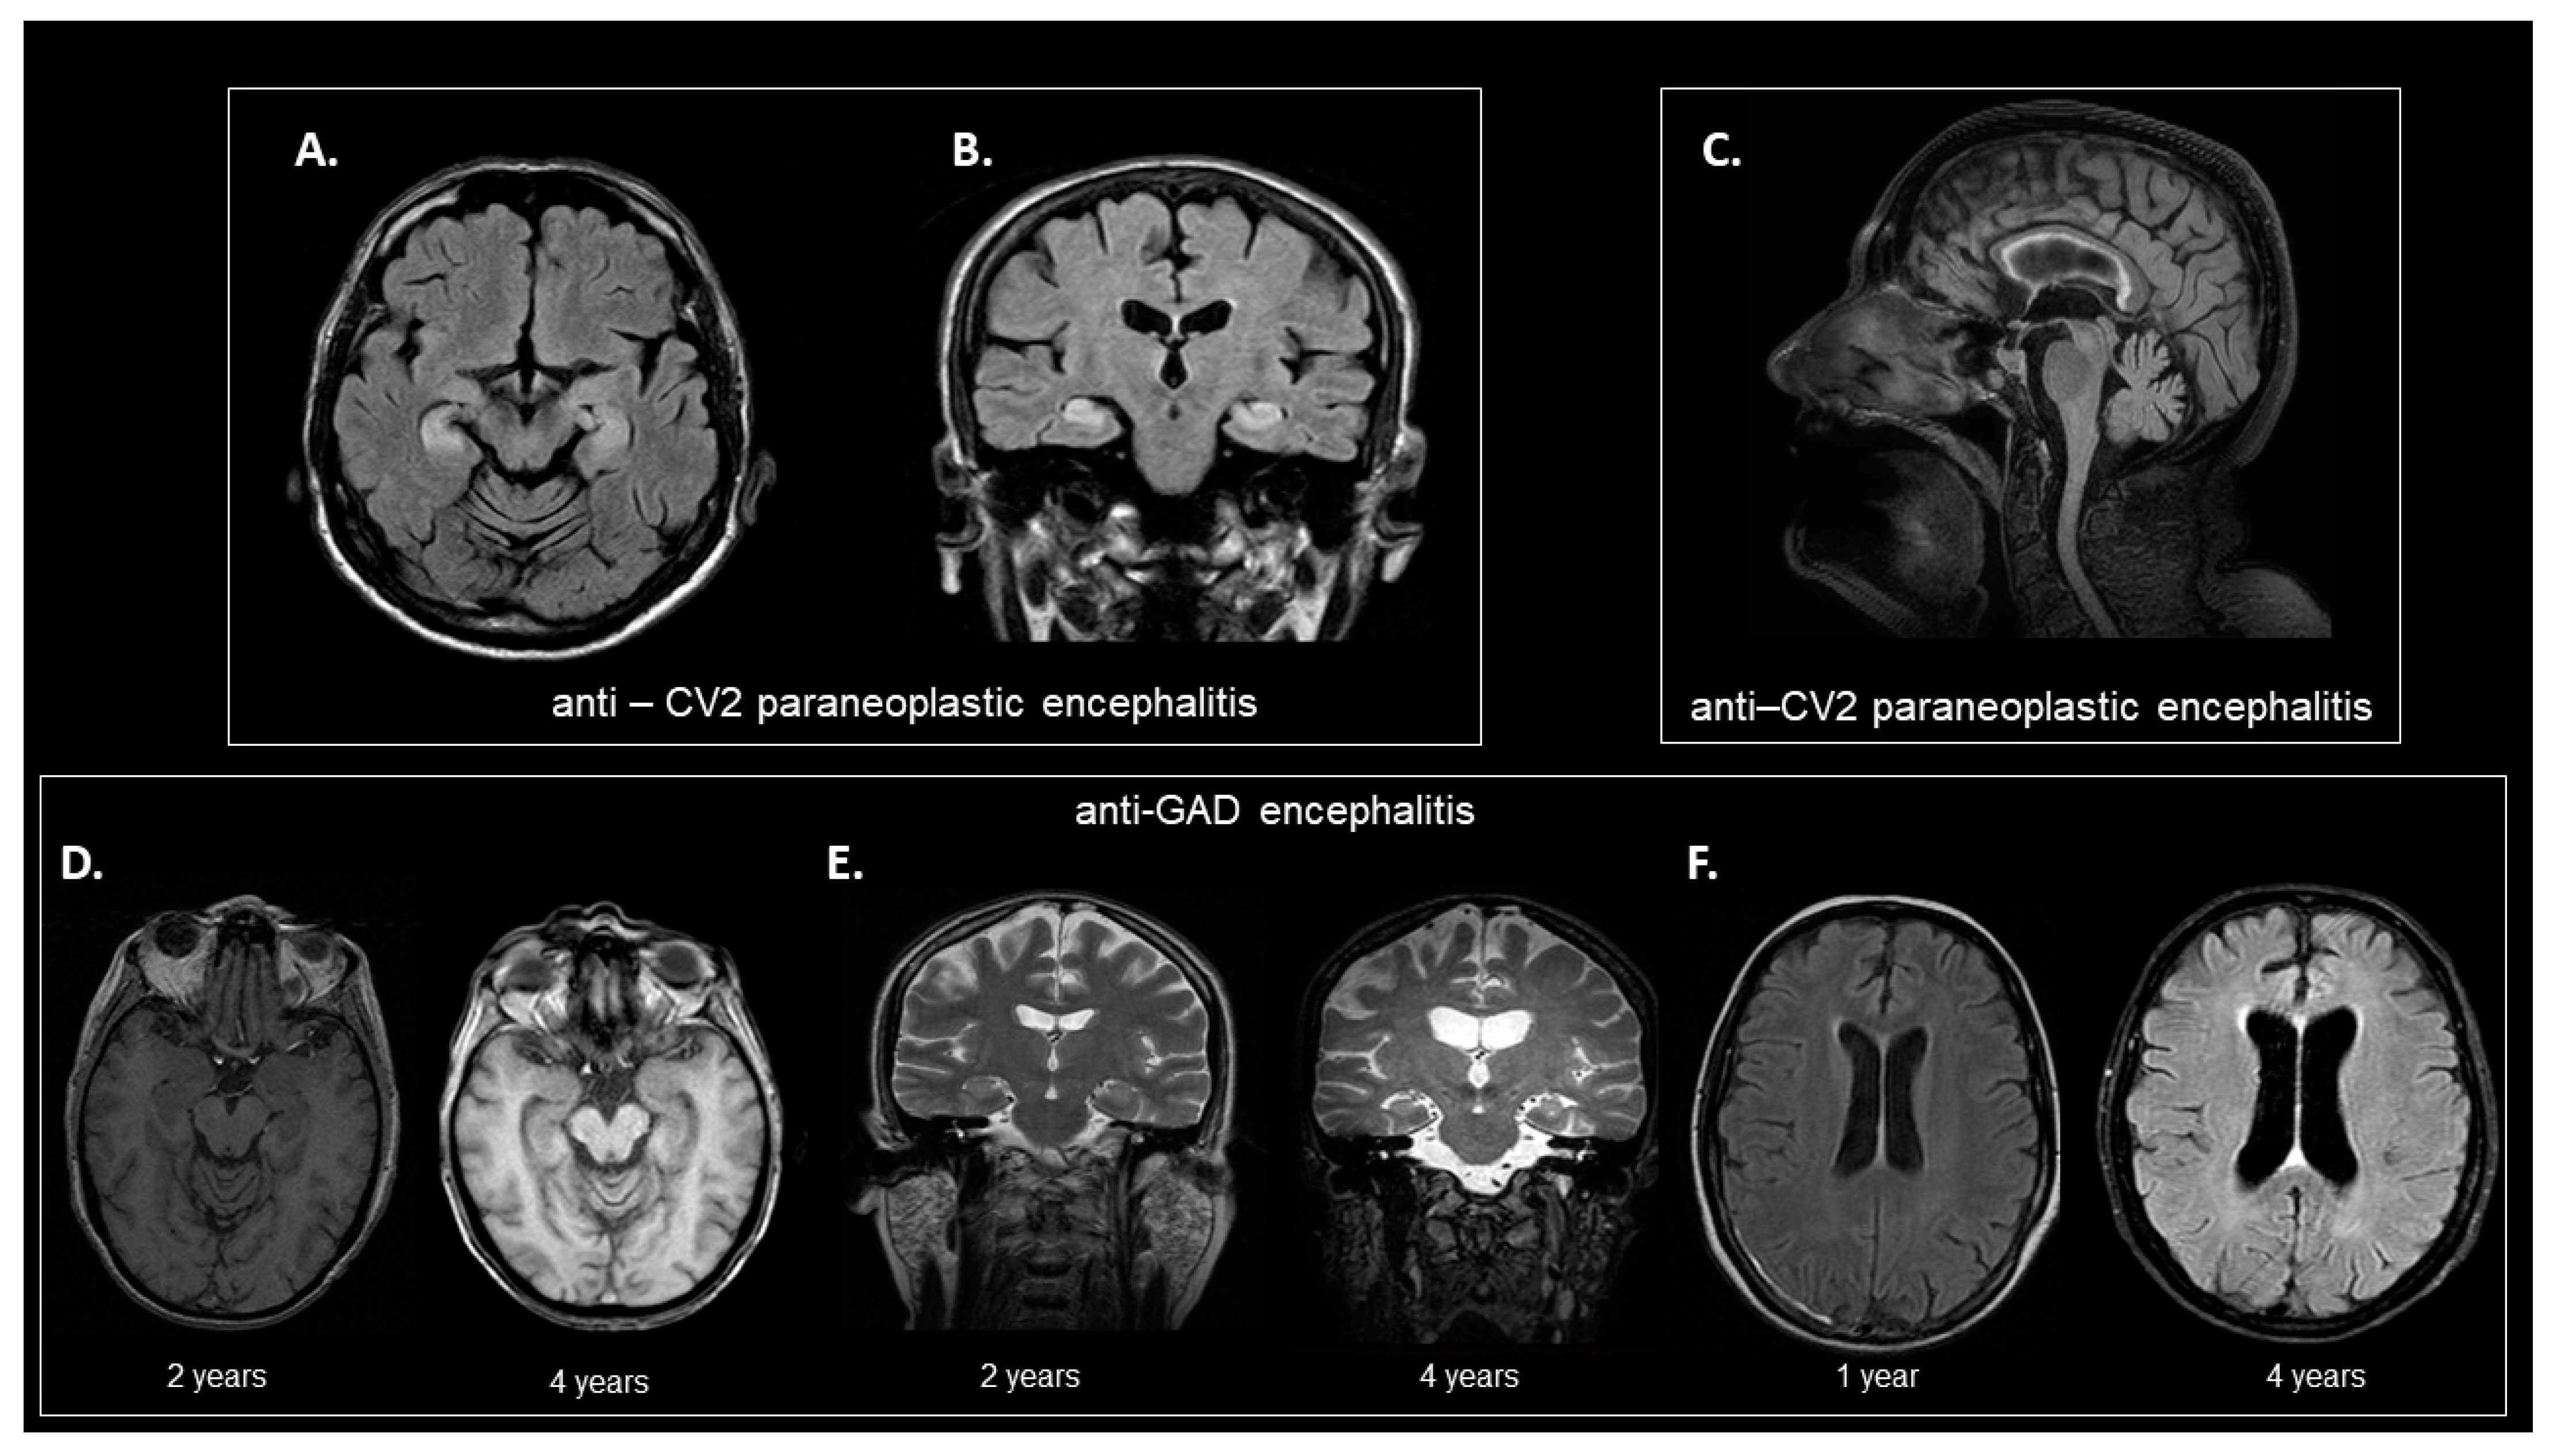

3.4. Brain MRI

| MRI findings | |

| Brain MRI scans | |

| Abnormal findings related to encephalitis, n (%) | 5 (23.81) |

| Significant atrophic changes, disproportionate to age, n (%) | 2 (9.52) |

| Basal ganglia involvement, n (%) | 1 (4.76) |

| Hippocampal involvement, n (%) | 2 (9.52) |

| Gadolinium enhancement, n (%) | 0 |